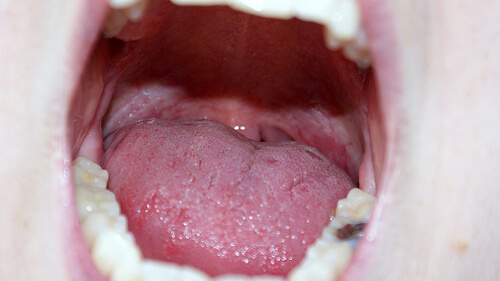

흔히 겪는 구강 문제 치료법

이 글에서는 우리가 흔히 겪는 구강 문제 치료법에 대해 이야기해보려고 한다.

잇몸, 치근막 등의 조직이 치아나 입술, 점막까지 영향을 미쳐 많은 구강 내 합병증이 생길 수 있다. 충치, 구취, 치은염, 구강 궤양 같은 일반적인 구강 문제를 예방하기 위해서는 이런 부위들을 보호하고 관리하는 것이 중요하다.